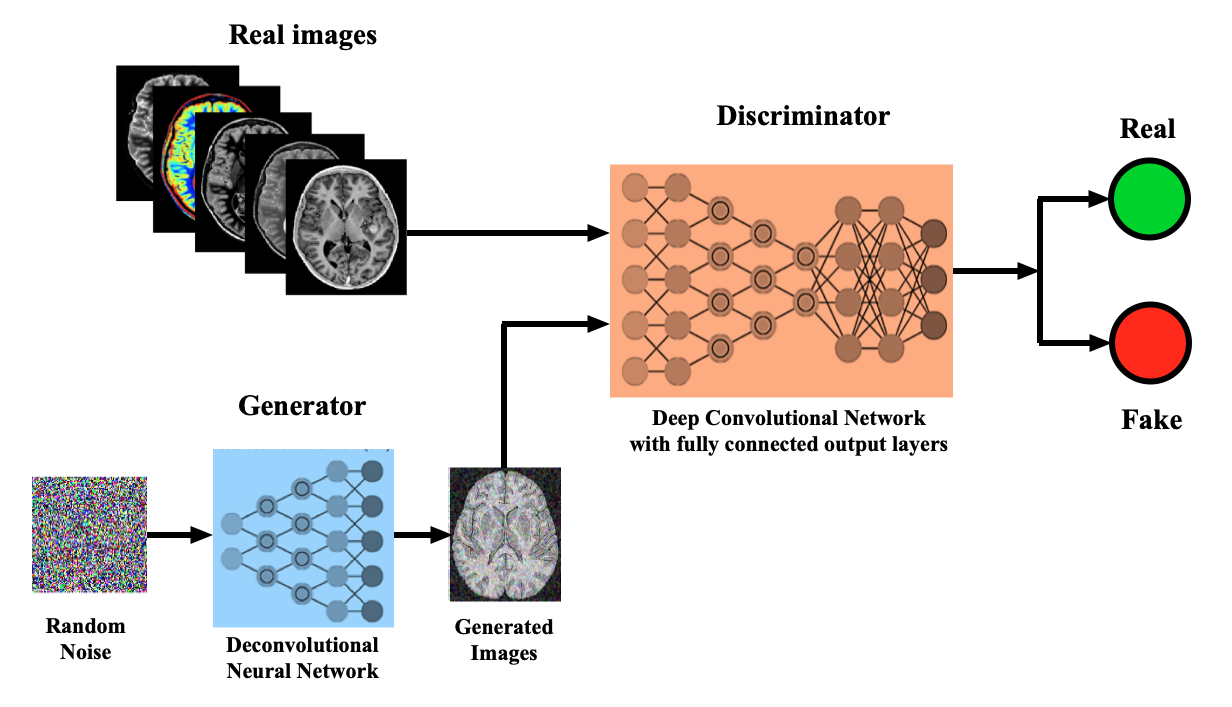

Генерация ЭКГ-изображения при помощи генеративно-состязательной нейронной сети (GAN)

Изучите существующие архитектуры GAN, такие как DCGAN, CycleGAN и StyleGAN, чтобы выбрать наиболее подходящую для ваших задач.